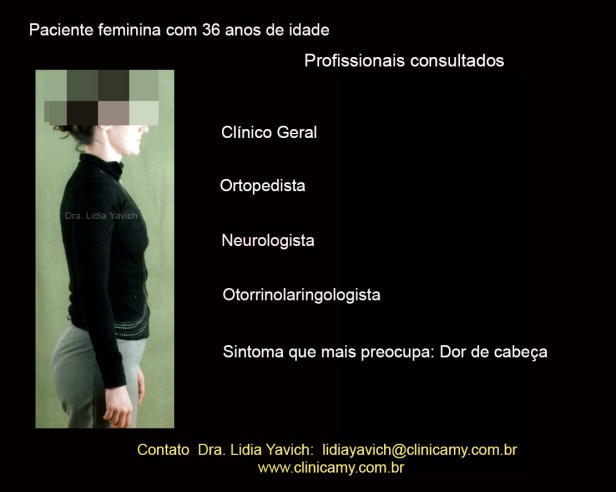

Paciente de sexo feminino com queixa principal de dor de cabeça se apresenta na clínica, encaminhada por um colega de trabalho que tinha sido tratado na clínica pelo mesmo motivo.

Paciente de sexo feminino com queixa principal de dor de cabeça se apresenta na clínica, encaminhada por um colega de trabalho que tinha sido tratado na clínica pelo mesmo motivo.

A queixa principal da paciente era de dor de cabeça com alta frequência. A paciente relata ter investigado a causa da dor e inclusive já tinha feito por solicitação do neurologista uma ressonância nuclear magnética de crânio que não acusou nenhuma anormalidade.

A paciente já tinha consultado com Neurologista, Otorrinolaringologista, Ortopedista e com o clínico geral.A paciente também refere dor de coluna.

A paciente já tinha consultado com Neurologista, Otorrinolaringologista, Ortopedista e com o clínico geral.A paciente também refere dor de coluna.